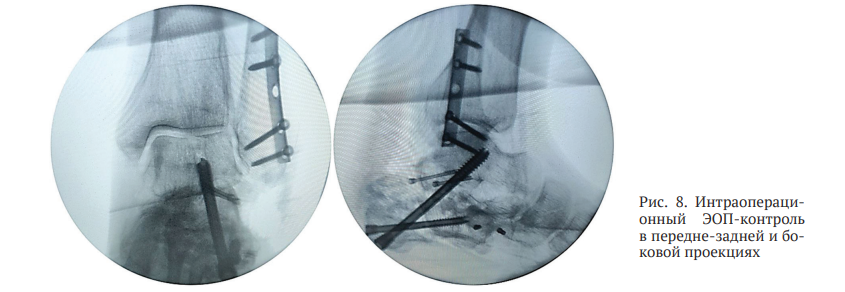

После изготовления индивидуального резекционного блока пациенту выполнено оперативное вмешательство с применением разработанного нами метода, в ходе которого достигнута планируемая коррекция деформации (рис. 8). Учитывая выраженное натяжение ахиллова сухожилия после репозиции костных фрагментов, пациенту осуществлена чрескожная ахиллотомия по Вульпиусу, в результате чего удалось достичь практически полного восстановления объема движений в левом голеностопном суставе.

Коррекция деформации пяточной кости выполнена в соответствии с предоперационным планированием. Положение костных фрагментов и установленной металлоконструкции оценено как удовлетворительное.